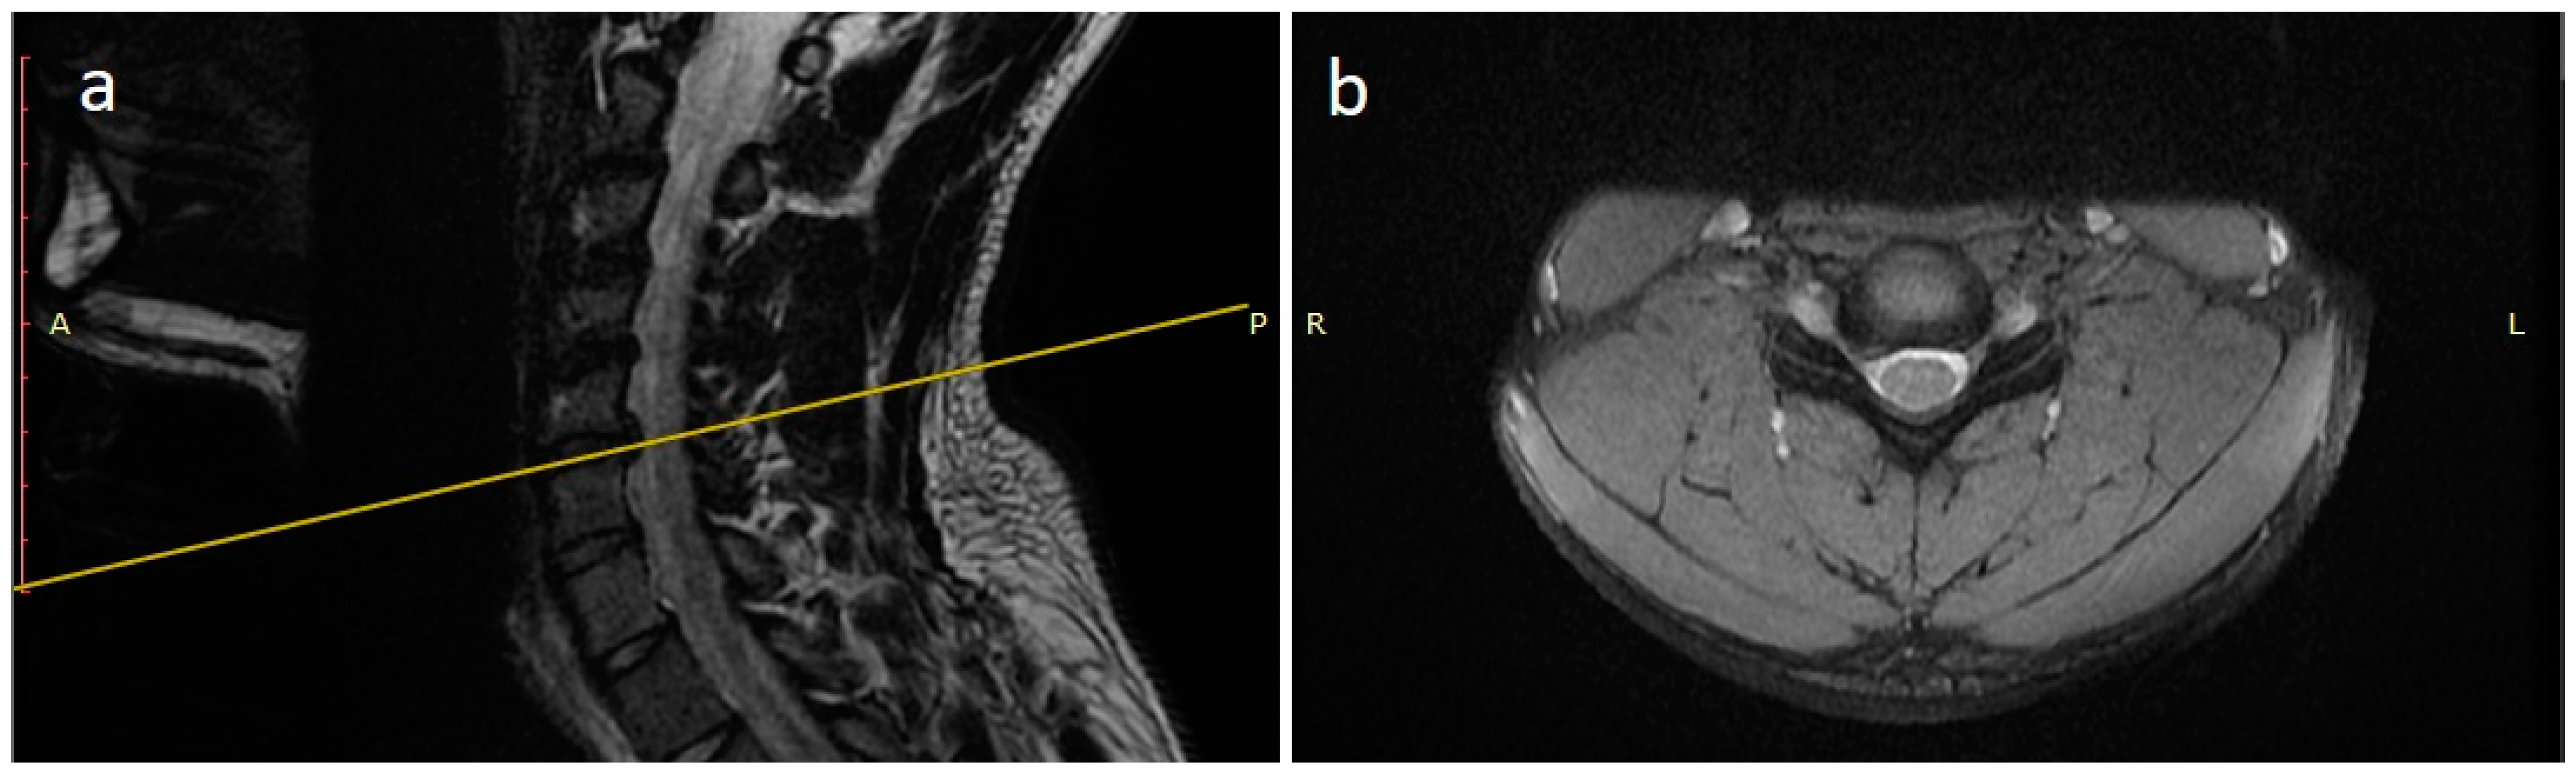

A 21 years-old male professional judoka started to feel neck pain radiating in the right C6 root dermatome with weakness in flexion-extension of the right forearm during a training activity. Due to the worsening of symptoms, the patient was suspended from the practice of judo. Moreover, he underwent a cervical spine MRI that showed the presence of C5-C6 disc herniation with C6 root compression and without spinal cord compression (Figure 2). After three months of conservative treatment (NSAIDs, steroids, physical therapy), surgical treatment was proposed. A standard C5-C6 ACDF with intraoperative neuromonitoring was performed with implantation of a stand-alone PEEK cage (CoRoent Small Interlock, NuVasive, San Diego, CA, USA) anchored with three titanium screws and packed with a biphasic calcium-phosphate bone graft substitute (AttraX Putty, NuVasive Inc., San Diego, CA, USA). The surgery was followed by a sudden relief from radicular pain, and the patient was discharged in two days. After a month of recovery, no motor or sensory deficits were detected at a neurosurgical follow-up visit. The CT of the cervical spine, three months after surgery, showed bone bridging as an initial sign of arthrodesis (Figure 3). In consideration of clinical and radiological outcomes, we recommended returning to training after 6 months and returning to competitive activities 7 months after surgery.

Figure 2.

MRI scan sagittal (a) and coronal (b) images of the cervical spine showing a C5-C6 disc herniation with C6 root compression.